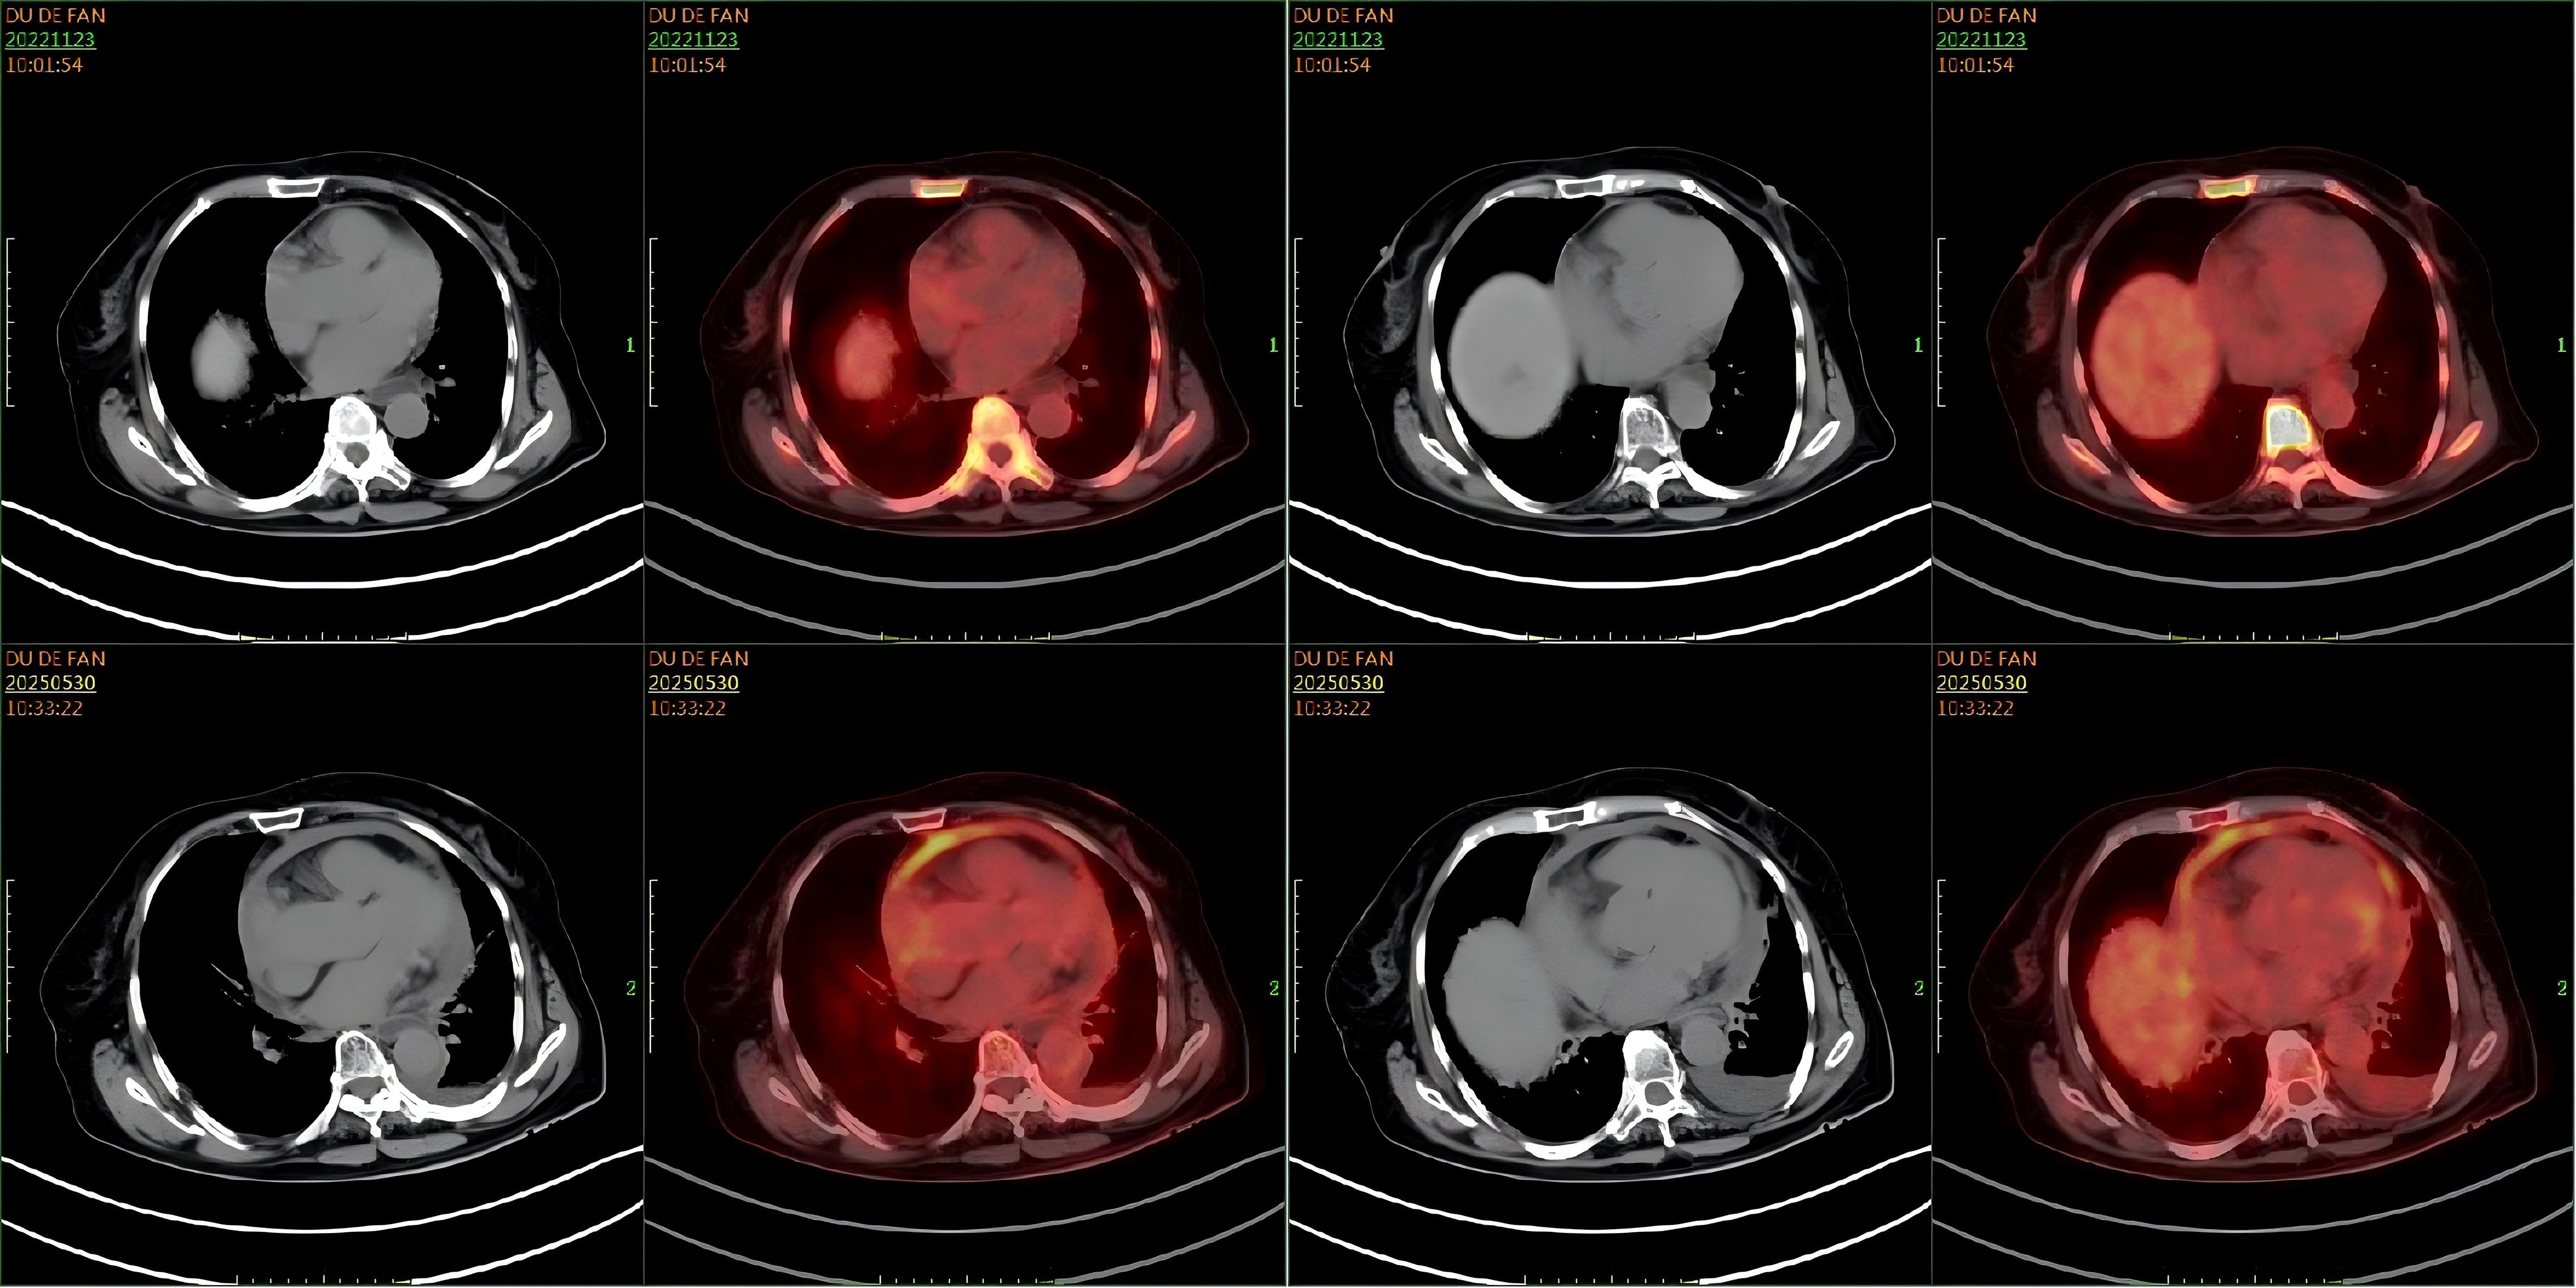

Fluid overload–associated large B-cell lymphoma (FO-LBCL) is a rare lymphoma that primarily involves serous body cavities (pleural, peritoneal, and pericardial spaces) without forming solid masses. Because FO-LBCL is uncommon, patients typically present with nonspecific symptoms—most frequently dyspnea from effusion—hindering early recognition and diagnosis. This study presents two cases of FO-LBCL and reviews the clinical characteristics, treatment regimens, and prognosis of 57 patients with FO-LBCL. Results showed that serous effusions involved the pleural cavity in 84.2% of cases, the pericardial cavity in 31.6%, and the peritoneal cavity in 21.1%. The most frequent presenting symptom was dyspnea (55.8%); other reported symptoms included chest tightness, gastric discomfort, fatigue, and lower-limb edema, reflecting respiratory, gastrointestinal, circulatory, and systemic involvement. Chemotherapy was the primary treatment (56.1%), most commonly the R-CHOP regimen. Univariate analysis identified the following factors as significantly associated with outcome: CD20 expression (P = 6 × 10-7), absence of CD138 expression (P = 0.0009), age > 65 years (P = 0.0015), LDH ≤500 U/L (P = 0.0064), presence of pleural effusion (P = 0.0099), CD79a expression (P = 0.0395), and use of rituximab-containing chemotherapy regimens (P = 0.0049). Our objectives are to characterize FO-LBCL comprehensively, clarify its differential diagnosis and management options, and address current gaps in clinical knowledge about this entity.